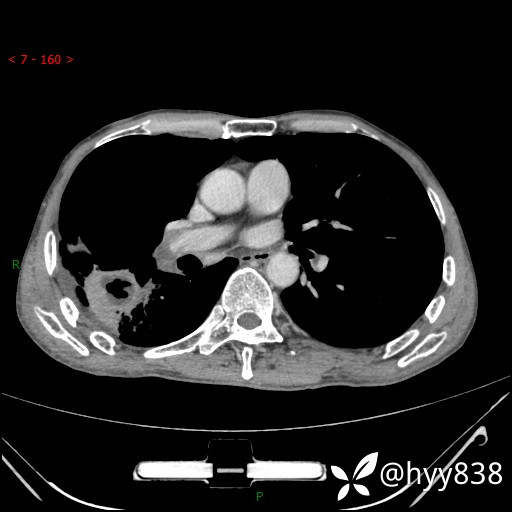

增强动脉期

静脉期